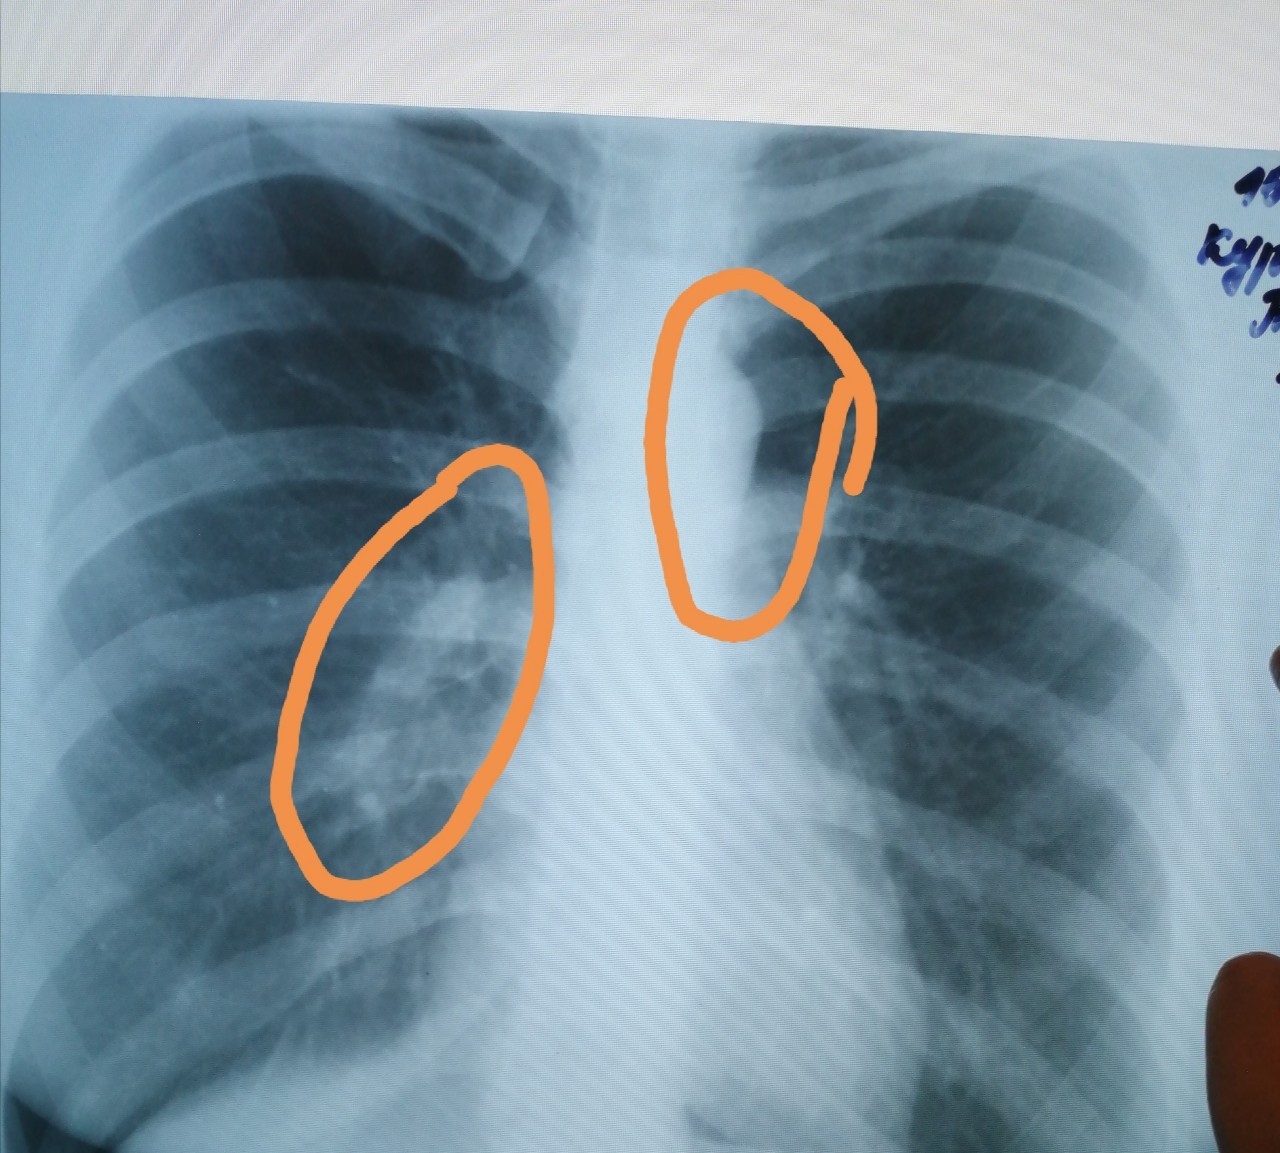

Нормальная рентгенограмма легких: что нужно знать

Раздел: Мудрость в объективе